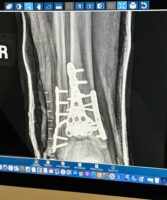

First Xray Post Surgery – February 2024

29 screws, 3 plates and another generous human’s bone holding everything together. The ER and Acute team at Banff Mineral Springs hospital made a horrific few days brighter. Dr. Heard’s magic along with the hardware placed will remain forever along with more scares to remind me of that which I am capable of overcoming.